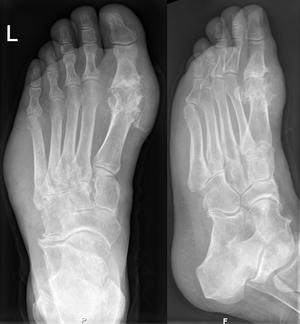

the MTP1 joint is absolutely destroyed caused by chronic rheumatism/ gout (depends on the clinical aspects). Accordingly we can also identify a swelling of the left foot which is normal for chronic rheumatism or gout. The lateral view also shows an exostosis of the Art. talonavicularis.